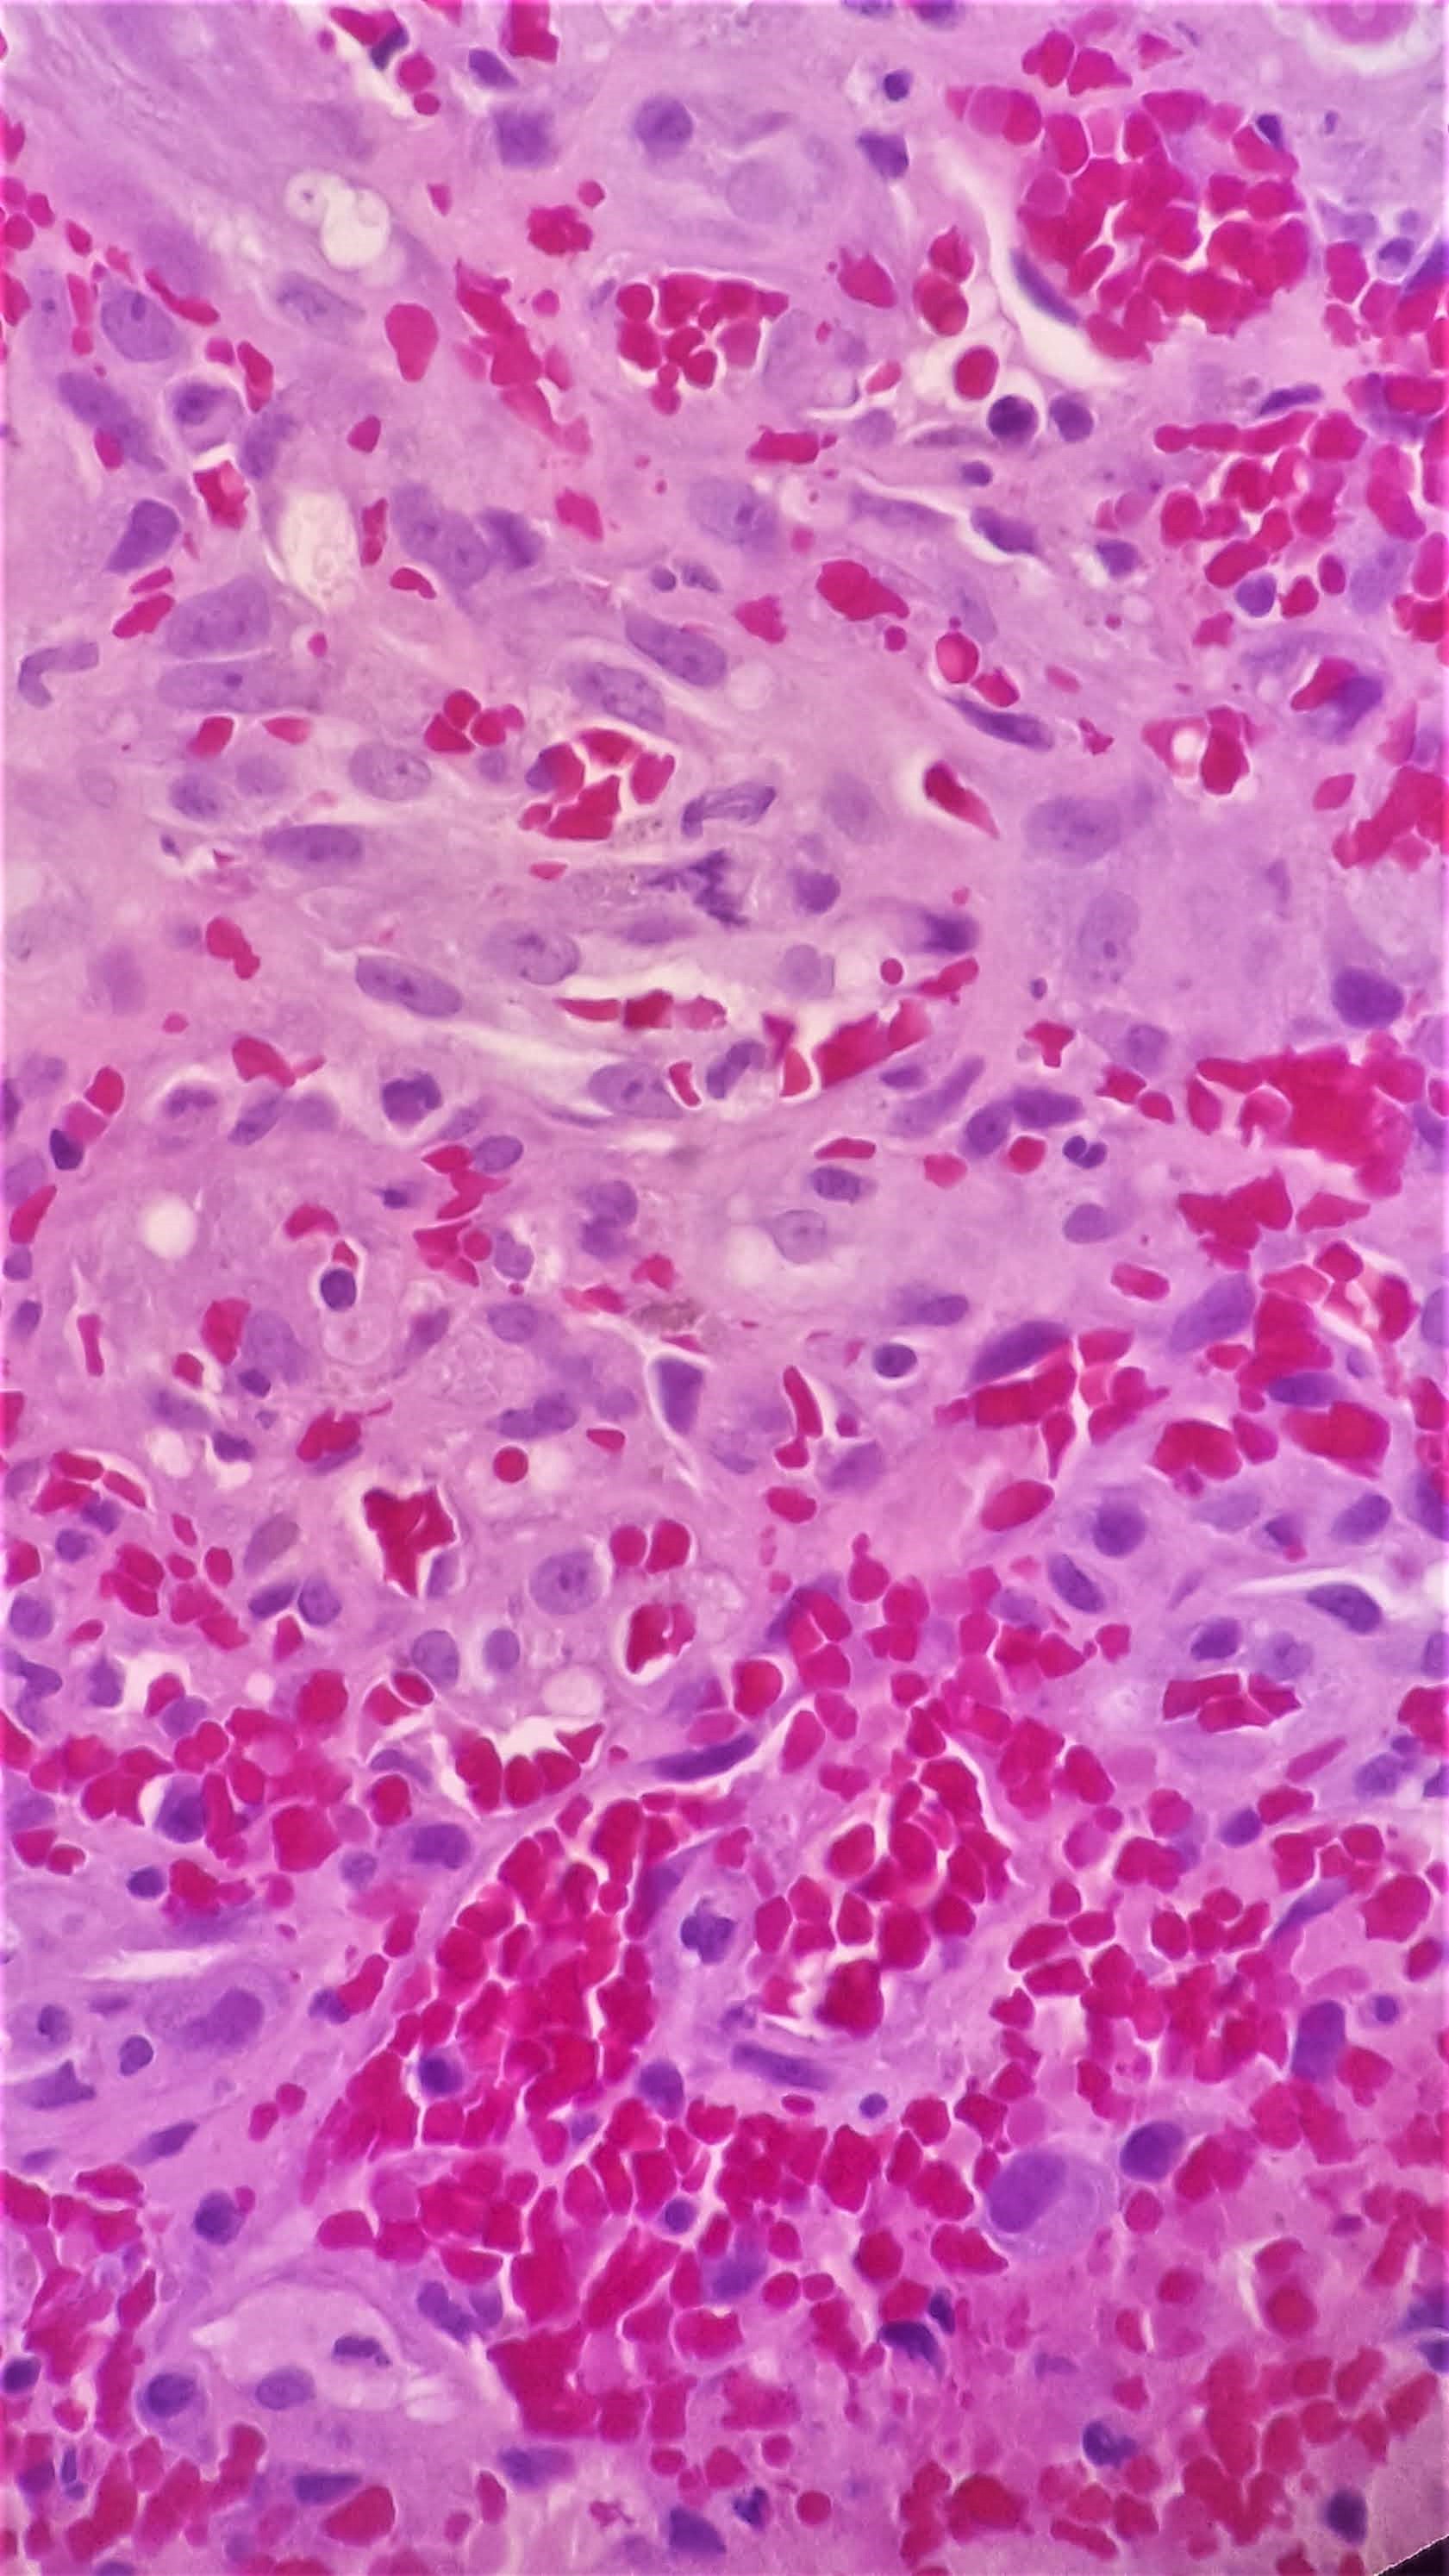

Microscopic examination reveals the following.

Histologically, Kaposi sarcoma is composed of monomorphic spindle cell proliferation arranged in a vague fascicular appearance with intervening slit-like spaces. Intracellular and extracellular eosinophilic PAS+ (diastase-resistant) hyaline globules are present as well as extravasated red blood cells. HHV8 (LANA) immunohistochemical stain can confirm the diagnosis. Treatment is variable based on the extent of the patient’s disease.

Histologically, CMV infected cells show enlarged cells (cytomegaly) and enlarged nuclei with ovoid intranuclear inclusions with a surrounding clear halo. This is classically called the “Owl’s Eye” appearance. Immunohistochemistry for CMV can confirm the presence of CMV infected cells. CMV infections can be treated with antiviral therapies and is important to notify the treating physician as early as possible.